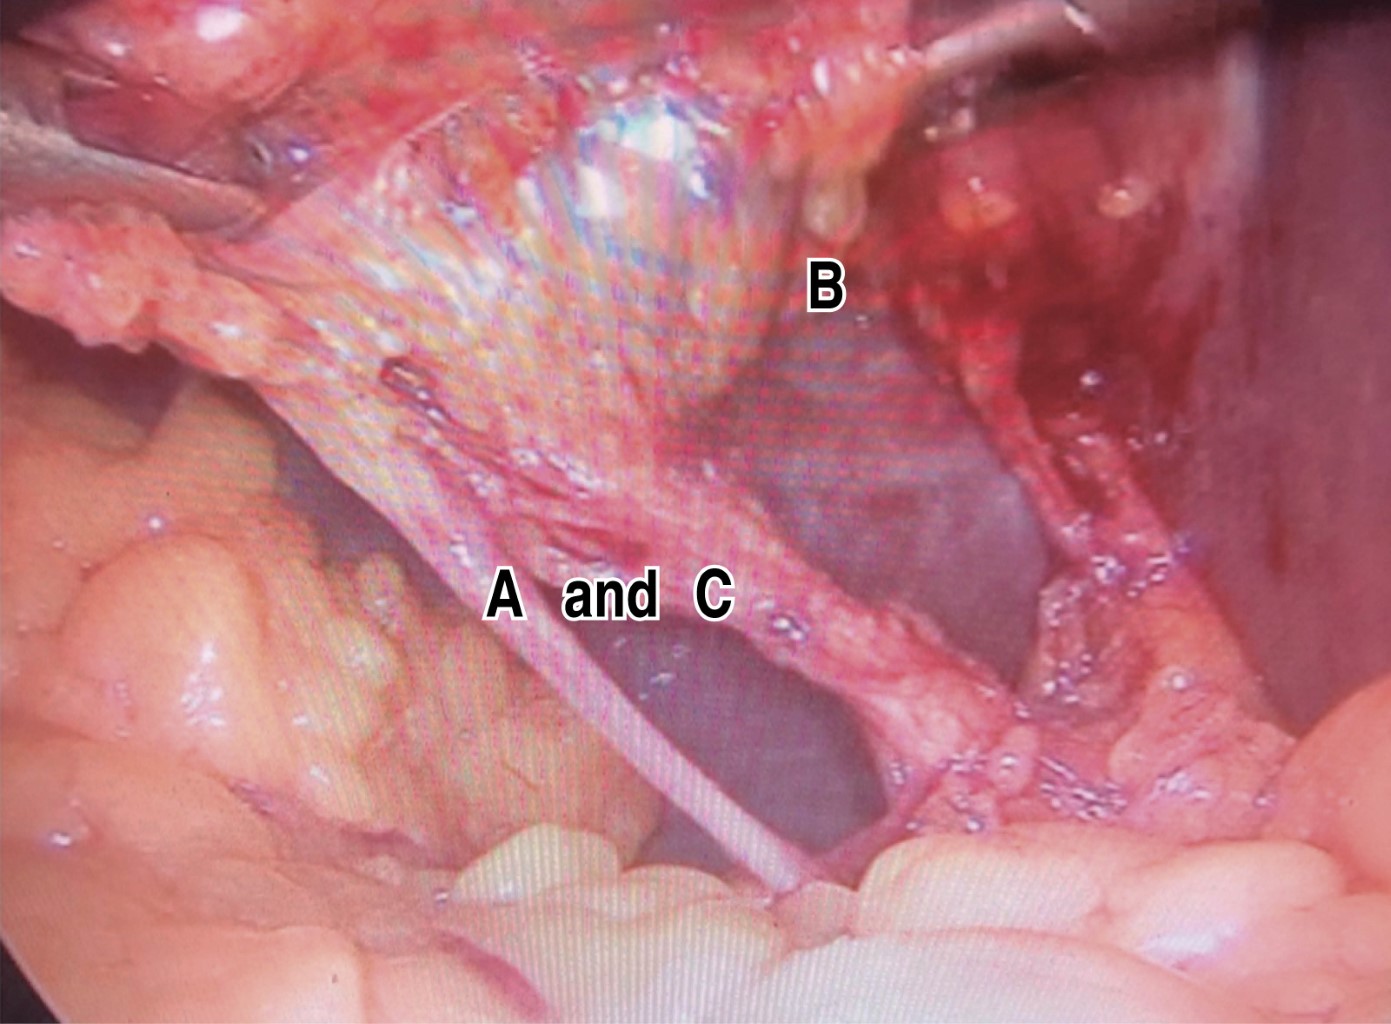

18. IN WHICH CASES IS IT RECOMMENDED TO PERFORM THE "CRITICAL SAFETY OVERVIEW"?

Always. Strasberg's critical view of safety has three dissection goals, which are maintained as the first recommendation for the culture of safe cholecystectomy. These goals consist of 1) complete dissection (anterior and posterior) of the hepatocystic triangle freeing fatty and fibrous tissue to observe and identify, in a complete manner, the cystic artery and cystic duct, 2) exposure of the lower third of the gallbladder bed, and 3) observe two and only two tubular structures entering the gallbladder corresponding to the cystic artery and cystic duct.66

By obtaining this safety-critical view, within this dissection space, up to 95% of the vascular variations and more than 80% of the anatomical variants of the extrahepatic bile duct can be identified.

If this critical safety view is not possible, it is recommended a salvage procedure, such as subtotal cholecystectomy and drainage, derivative cholecystostomy, or conversion to open surgery be considered 1,56,66,69,70,74-80 (Figure 1).

Percentage of agreement: 100%. Level of evidence: 1, grade: A, grade of recommendation: strong.